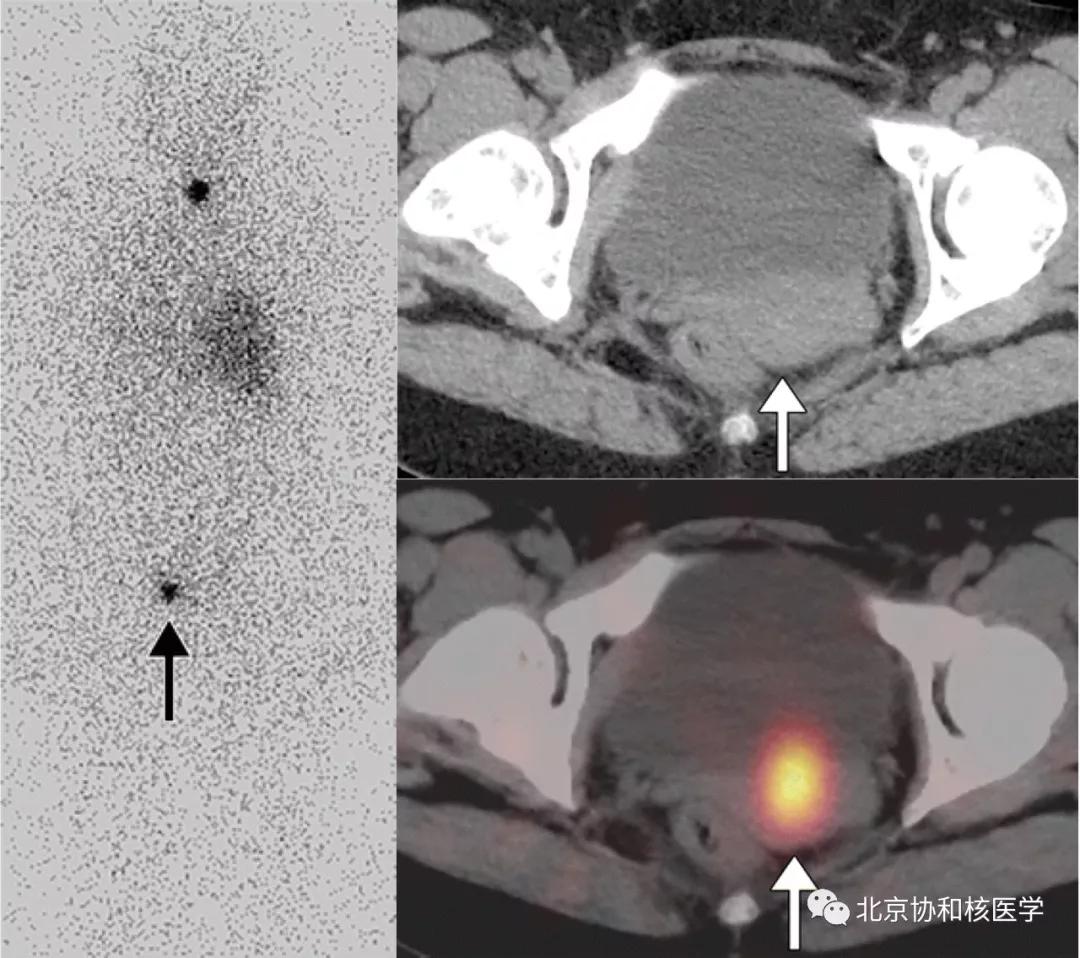

39岁女性,恶性卵巢甲状腺肿病史,行右侧卵巢切除术、甲状腺切除术、碘131治疗,碘扫可见残余甲状腺摄取、盆腔转移灶摄取及肝转移灶摄取: